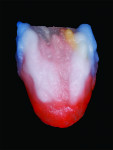

Further enhancement of the incisal two-thirds was undertaken to create internal characterization by applying a layer of MM light and MM yellow-orange (Figure 15). The author then placed a blue translucent layer on the mesial and distal incisal edges and a white blue translucent layer over the mesial and distal line angle areas, found naturally on the contra-lateral side (Figure 16). A cervical translucent material was applied onto the gingival one-third while the incisal two-thirds was covered with a mixture of T1 and OE4 (Figure 17).